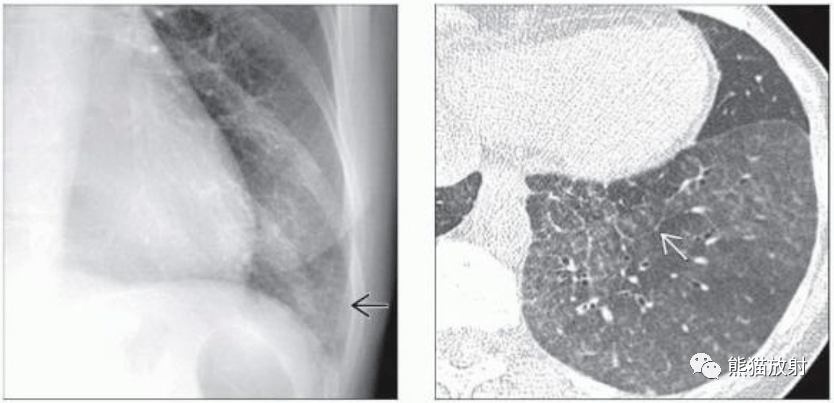

间质性肺炎x片,

kaposi肉瘤淋巴细胞间质性肺炎丨影像表现